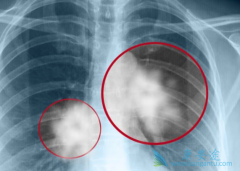

自2017年奥希替尼在中国上市以来,就成为了许多肺癌晚期EGFR阳性患者的“救命稻草”,因为它解决了第一代靶向药耐药的问题,作为EGFR阳性患者的二线、三线治疗,不仅延长患者生存期,还大大提高了患者的生活质量。那么 肺癌晚期特效药 奥希替尼的疗效究 ...